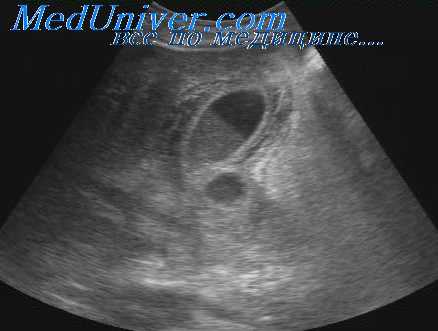

- УЗИ печени и желчного пузыря. Ультразвуковое исследование позволяет обнаружить структурные изменения печеночной паренхимы (повышение или снижение эхогенности ткани), утолщение стенки желчного пузыря, дилатацию протоков. При сонографии определяют конкременты, которые вызывают механический блок выделения желчи в кишечник.